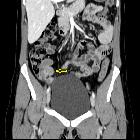

Endometriosis

of the Appendix. CT exam depicted a nonspecific focal mass (yellow arrow) in the distal third of the appendix without any evidence of inflammation